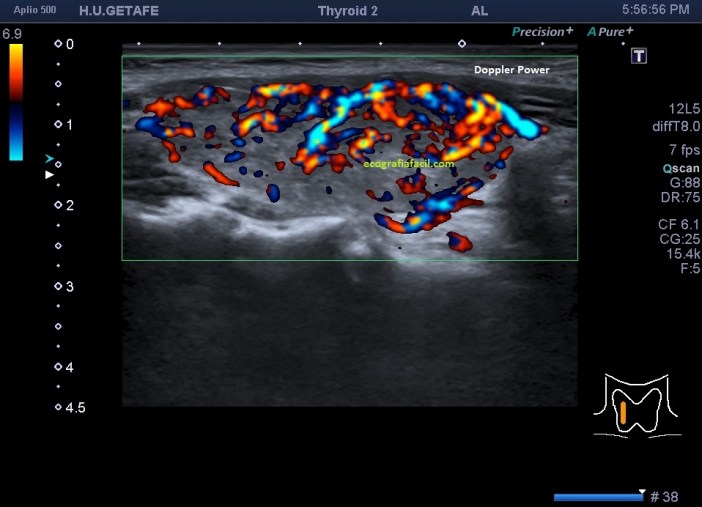

En la imagen 7 tienes el corte del lado contralateral del tiroides, donde con el modo angio activado, puedes ver además que ese lóbulo tiene más actividad vascular que el izquierdo.

7